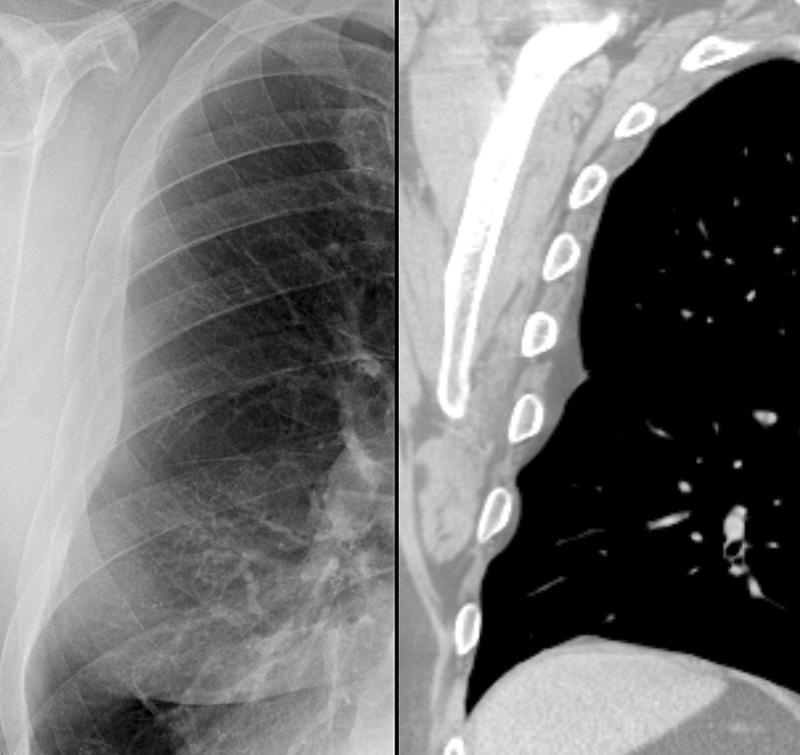

subpleural - fat